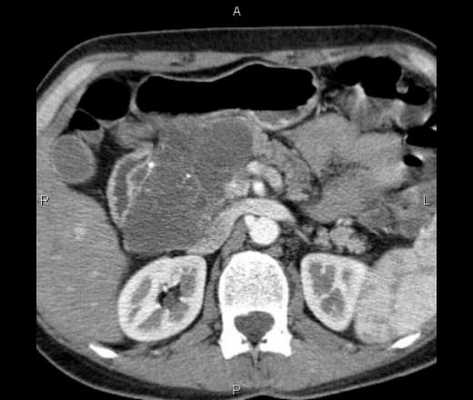

- Мультиспиральную компьютерную томографию органов брюшной полости;

КТ брюшной полости является современным и точным рентгенологическим способом диагностики органов, расположенных в брюшной области. Во время обследования происходит томографическое, то есть, послойное сканирование исследуемой зоны. Современные мультспиральные томографы способны за один оборот сканера делать от 32 до 640 срезов

КТ брюшной полости является современным и точным рентгенологическим способом диагностики органов, расположенных в брюшной области. Во время обследования происходит томографическое, то есть, послойное сканирование исследуемой зоны. Современные мультспиральные томографы способны за один оборот сканера делать от 32 до 640 срезов, а мощный компьютер может создать трехмерные реконструкции всех анатомических структур области живота. Данные КТ снимков позволяют выявить воспалительные процессы и опухолевые изменения в костных и мягкотканных структурах.

Процедура компьютерной томографии органов брюшной полости проходит по двум базовым протоколам - нативная и контрастная. МСКТ с контрастным усилением предполагает использование контрастных препаратов на базе йода, которые улучшает тканевую контрастность на томограммах и позволяет определить новообразования на этапе развития. Кроме того, существует агиографическая форма обследования (КТ брюшной аорты и сосудов) области живота, когда врачи прицельно оценивают сосудистую систему брюшной полости.